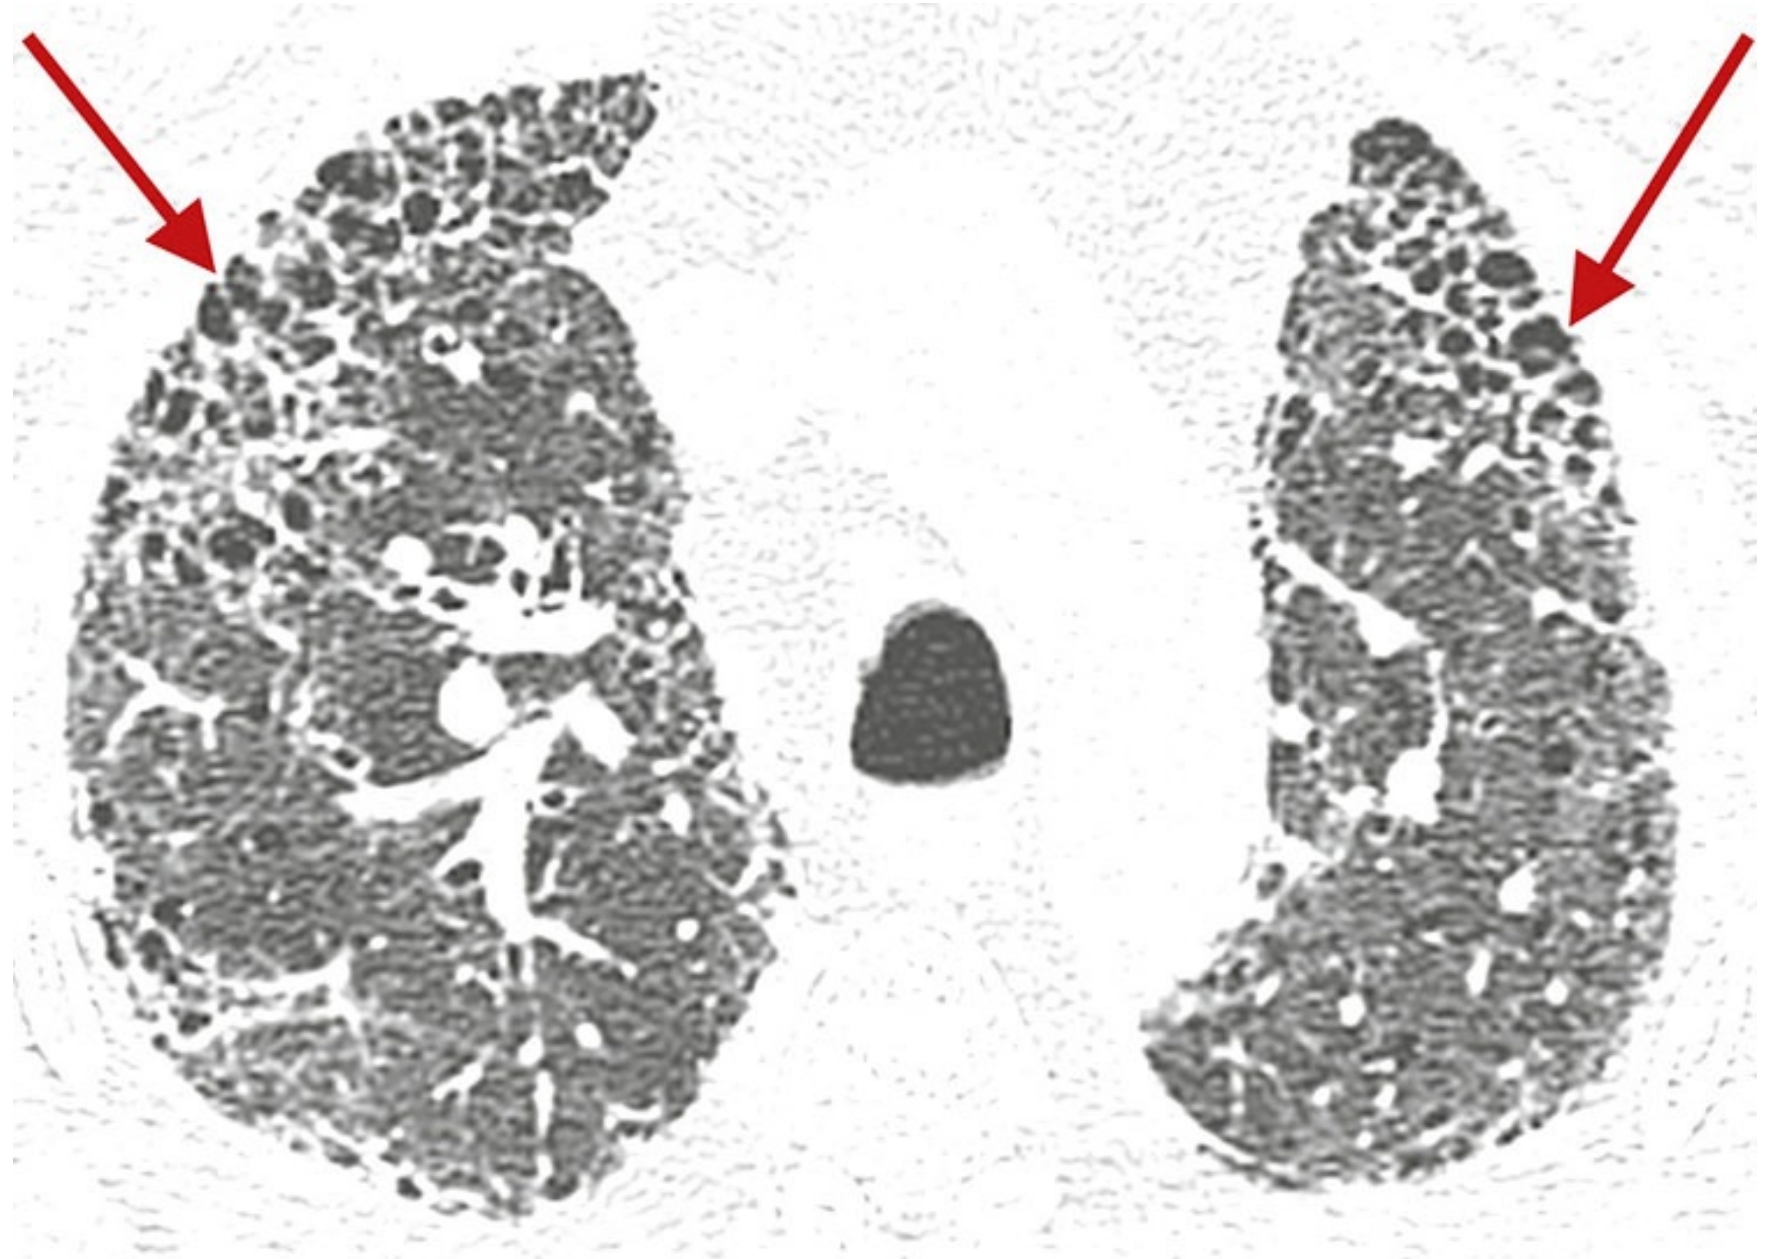

ffd7bb23e755e95335b0c12dc29c866a.png

普通型间质性肺炎(UIP)的典型表现。

A.伴有特发性肺纤维化的UIP模式患者,HRCT显示广泛的胸膜下和肺基底分布为主的蜂窝征;

B.散在分布的胸膜下蜂窝征(红箭),与相对正常的肺组织(蓝箭)相间;

C.俯卧位HRCT显示UIP患者的蜂窝征(箭),可为单层(黄箭)或多层(蓝箭);

D.早期UIP表现为轻度的胸膜下网状影和蜂窝征,虽然程度轻微,但仍可明确判定蜂窝征(箭)。